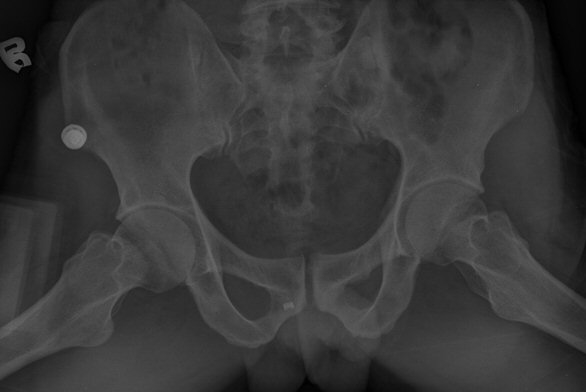

´Ü¼ø¹æ»ç¼±°Ë»ç

ÃÊÁø ½Ã ½ÃÇàÇÑ ¹æ»ç¼± ÃÔ¿µ»ó ÀüÇÏÀ屨 ºÎÀ§¿¡¼­ ¼®È¸È­ À½¿µÀÌ °üÂûµÇ°í, 3ÁÖ ÈÄ ½ÃÇàÇÑ ÃÔ¿µ¿¡¼­

¼®È¸È­ À½¿µ ¼Ò½ÇÀÌ È®ÀεÊ.